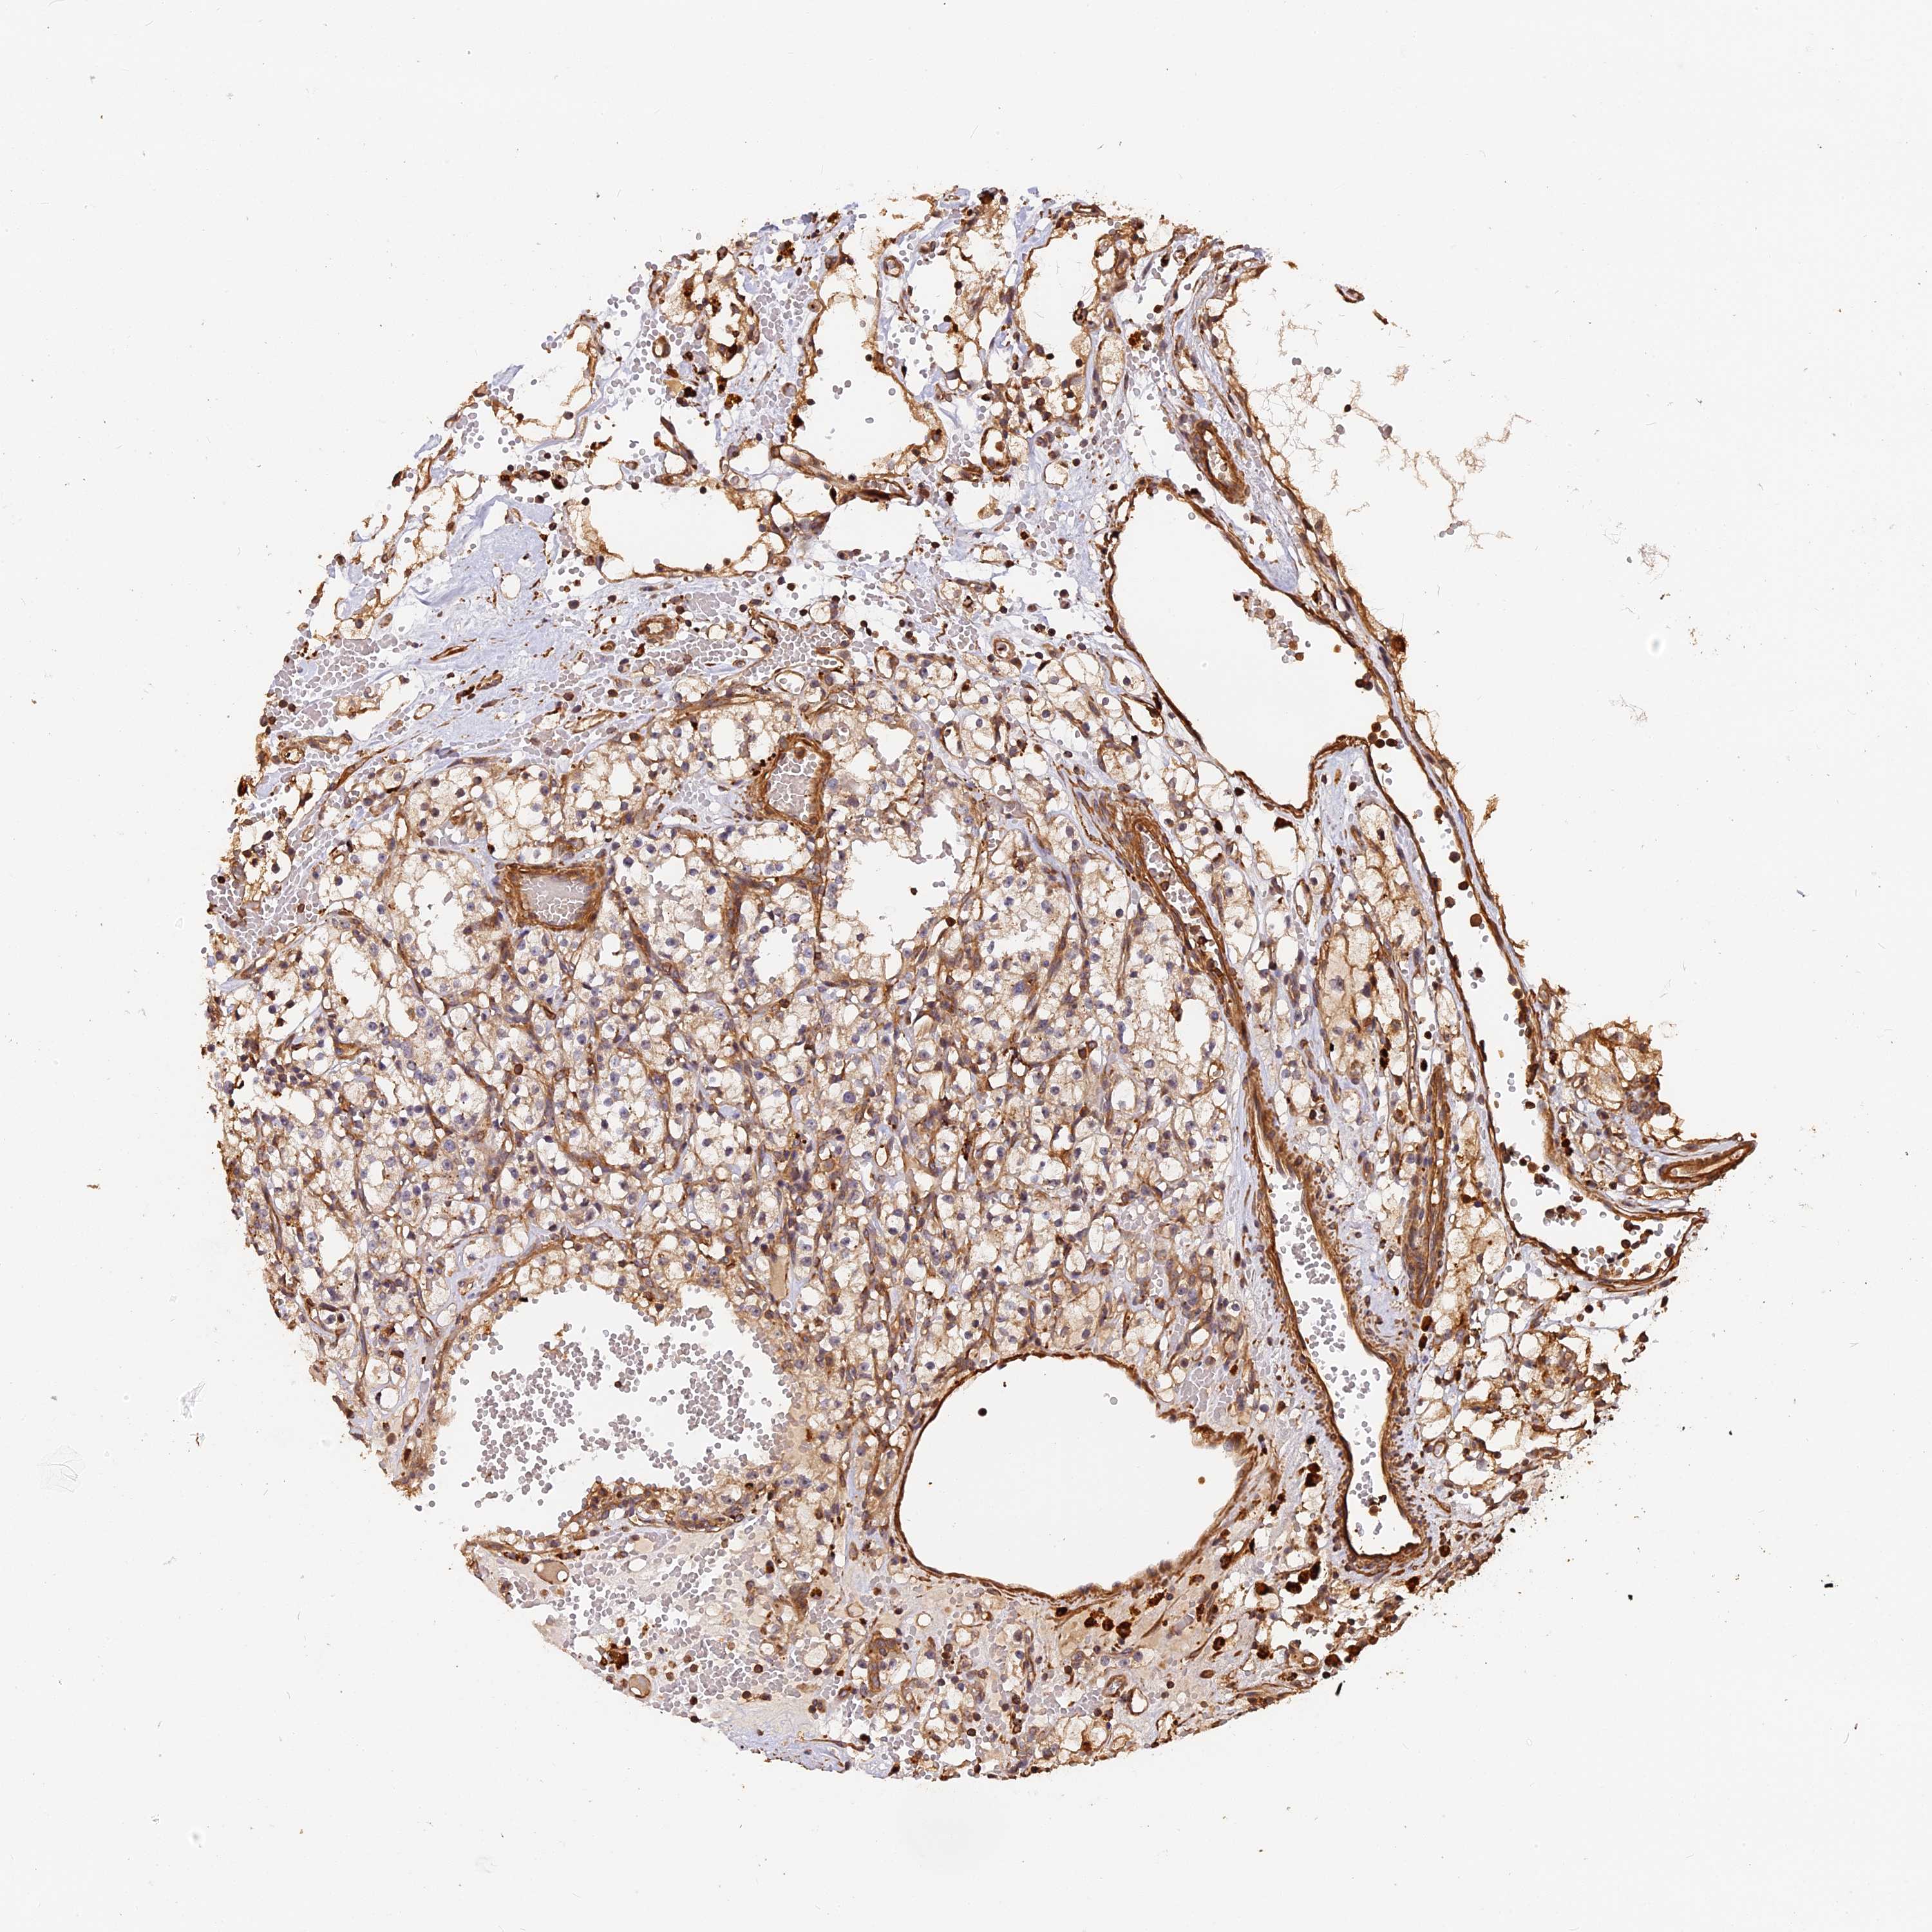

KIDNEY RENAL CLEAR CELL CARCINOMA (VALIDATION) - Interactive survival scatter ploti

The Survival Scatter plot shows the clinical status (i.e. dead or alive) for all individuals in the patient cohort, based on the same data that underlies the corresponding Kaplan-Meier plots. Patients that are alive at last time for follow-up are shown in blue and patients who have died during the study are shown in red.

The x-axis shows the expression levels (FPKM) of the investigated gene in the tumor tissue at the time of diagnosis. The y-axis shows the follow-up time after diagnosis (years). Both axes are complimented with kernel density curves demonstrating the data density over the axes. The top density plot shows the expression levels (FPKM) distribution among dead (red) and alive patients (blue). The right density plot shows the data density of the survived years of dead patients with high and low expression levels respectively, stratified using the cutoff indicated by the vertical dashed line through the Survival Scatter plot. This cutoff is automatically defined based on the FPKM cutoff that minimizes the p-score. The cutoff can be changed by dragging the vertical line or by entering a cutoff value in the square labeled "Current cut-off".

Under the Survival Scatter plot the p-score landscape (black curve; left axis) is shown together with dead median separation (red curve; right axis). Dead median separation is the difference in median mRNA expression between patients who have died with high and low expression, respectively. It is calculated as follows: median FPKM expression of dead patients with high expression - median FPKM expression of dead patients with low expression. This is intended to aid the user in visually exploring custom cutoffs and the associated p-scores and dead median separation.

Individual patient data is displayed and can be filtered by clicking on one or more of the category buttons on the top of the page. Categories describing expression level and patient information include: high, low, alive, dead, female, male and tumor stages. The scale of the x-axis can be toggled between linear and log-scale by clicking on the "x log" button. Mouse-over function shows TCGA ID, patient information and mRNA expression (FPKM) for each patient.

& Survival analysisi

Kaplan-Meier plots summarize results from analysis of correlation between mRNA expression level and patient survival. Patients were divided based on level of expression into one of the two groups "low" (under cut off) or "high" (over cut off). X-axis shows time for survival (years) and y-axis shows the probability of survival, where 1.0 corresponds to 100 percent.

MMP15 is not prognostic in Kidney Renal Clear Cell Carcinoma (validation)

Best expression cut offi

Based on the FPKM value of each gene, patients were classified into two groups and association between prognosis (survival) and gene expression (FPKM) was examined. The best expression cut-off refers the FPKM value that yields maximal difference with regard to survival between the two groups at the lowest log-rank P-value. Best expression cut-off was selected based on survival analysis .

When clicking on this number, the vertical dashed line indicating cut-off, the interactive survival plot, and the Kaplan-Meier curve will be adjusted to show results based on the best expression cut-off.

: 11.33

TCGA RNA samplesi

RNA-seq data is reported as average FPKM (number Fragments Per Kilobase of exon per Million reads), generated by the The Cancer Genome Atlas (TCGA) .

Normal distribution across the dataset is visualized with box plots, shown as median and 25th and 75th percentiles. Points are displayed as outliers if they are above or below 1.5 times the interquartile range. FPKM values of the individual samples are presented next to the box plot.

Average pTPM 15.4

Number of samples 100